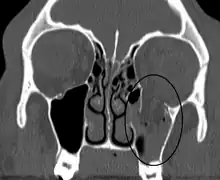

| An orbital blowout fracture of the floor of the left orbit. | |

An orbital blowout fracture is a traumatic deformity of the orbital floor or medial wall that typically results from the impact of a blunt object larger than the orbital aperture, or eye socket.[1] Most commonly this results in a herniation of orbital contents through the orbital fractures.[1] The proximity of maxillary and ethmoidal sinus increases the susceptibility of the floor and medial wall for the orbital blowout fracture in these anatomical sites.[2] Most commonly, the inferior orbital wall, or the floor, is likely to collapse, because the bones of the roof and lateral walls are robust.[2] Although the bone forming the medial wall is the thinnest, it is buttressed by the bone separating the ethmoidal air cells.[2] The comparatively thin bone of the floor of the orbit and roof of the maxillary sinus has no support and so the inferior wall collapses mostly. Therefore, medial wall blowout fractures are the second-most common, and superior wall, or roof and lateral wall, blowout fractures are uncommon and rare, respectively. They are characterized by double vision, sunken ocular globes, and loss of sensation of the cheek and upper gums from infraorbital nerve injury.[3]

Imaging

Thin cut (2-3mm) CT scan with axial and coronal view is the optimal study of choice for orbital fractures.[16][17]

Plain radiographs, on the other hand, do not have the sensitively capture blowout fractures.[18] On Water's view radiograph, polypoid mass can be observed hanging from the floor into the maxillary antrum, classically known as teardrop sign, as it usually is in shape of a teardrop. This polypoid mass consists of herniated orbital contents, periorbital fat and inferior rectus muscle. The affected sinus is partially opacified on radiograph. Air-fluid level in maxillary sinus may sometimes be seen due to presence of blood. Lucency in orbits (on a radiograph) usually indicate orbital emphysema.[4]